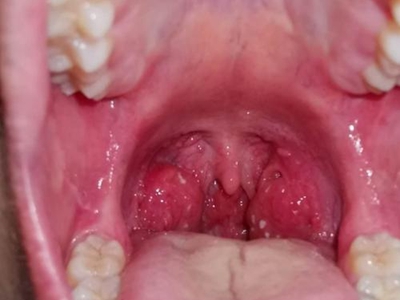

扁桃体

红肿 · 化脓

淋菌性咽炎扁桃体肿大上面有脓点图

淋菌性咽炎患者嘴巴里的两侧扁桃体严重肿大,快要堵塞咽喉处,由于充血导致扁桃体通体发红。左侧扁桃体偏上位置形成了一个凸起的脓点,颜色发白。